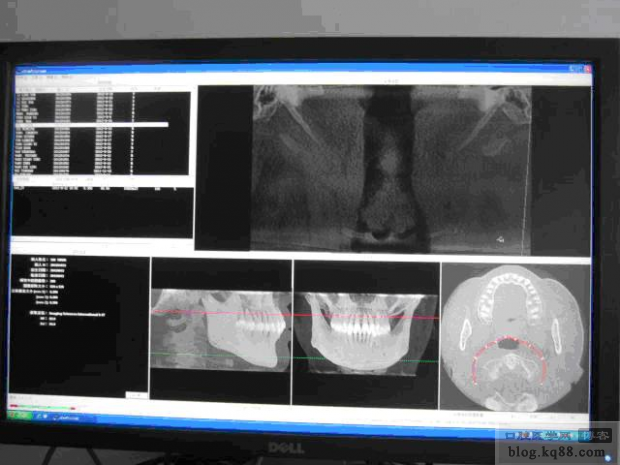

圖3通過層次閾的調(diào)整把兩側(cè)的莖突調(diào)整到一個層面上

圖3